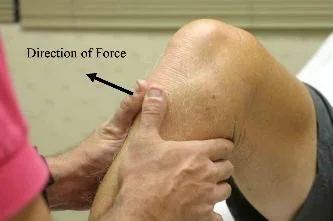

Cruciate Ligament Testing

- Anterior/Posterior Drawer Test

- Lachman’s test

- Sagging sign: indicates Posterior cruciate ligament tear